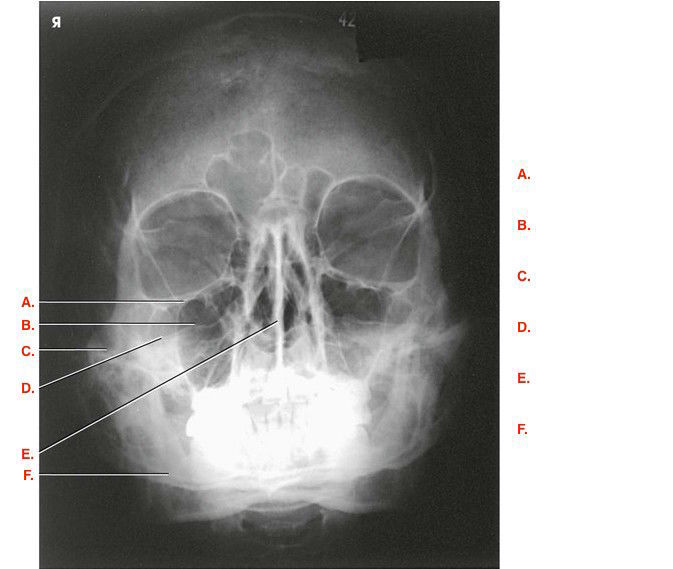

Question 1

Question

Label the image

Image:

Answer

frontal sinus

nasal bone

sella turcica

maxillary sinus

external acoustic meatus

maxilla

mandible